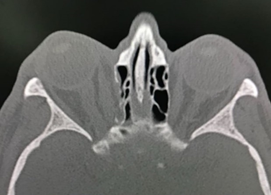

However, during the second postoperative day, and after performing a hemodialysis session, the patient presented increased edema, proptosis and hemorrhagic chemosis that exceeded the palpebral margin, limitation for ocular closure, right ophthalmoplegia and decreased vision. visual acuity to the point of not perceiving light, so he was assessed by the ophthalmology service who performed an emergency lateral canthotomy and a new CT scan of the orbits was requested, where a hematoma with dimensions of 1.9 x 2.1 x 3.0 cm, and an approximate volume of 6.2 cm3 (see Figures 2 and 3), persistence of sinking of the right lamina papyracea and no evidence of fracture of the maxillo-malar processes, or zygomatic arches, but a slight angulation was evidenced from the posterolateral wall of the right maxillary antrum; Considering a picture of retrobulbar hematoma in the right eye secondary to an open reduction of the floor of the orbit.

Figure 2 Right retrobulbar hematoma (black arrow). Taken from the radiological images of the patient.